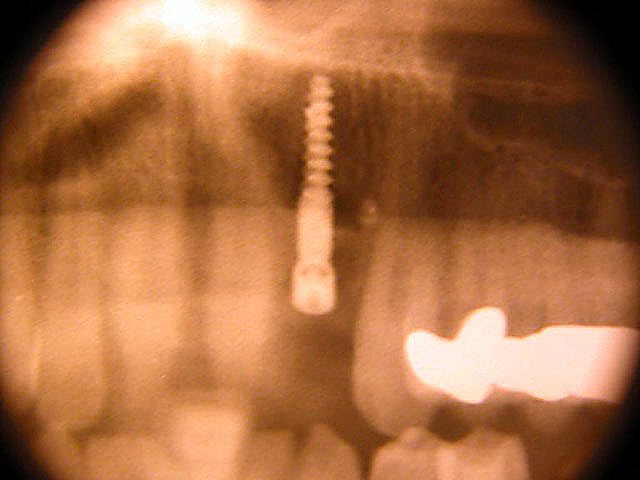

Implantation mit Knochenblock-Implantaten: